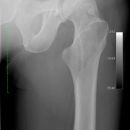

pertrochantäre Femurfraktur